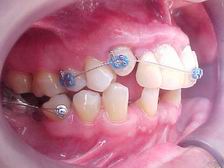

Preparação para instalação do "aparelho ortodôntico" (canino reconstruído em resina rápida autopolimerizável, retida por fio metálico sobre raiz residual)

Início do tratamento ortodôntico. Com a extrusão do canino estaremos induzindo ao nivelamento ósseo para a instalação de implante nesse local.